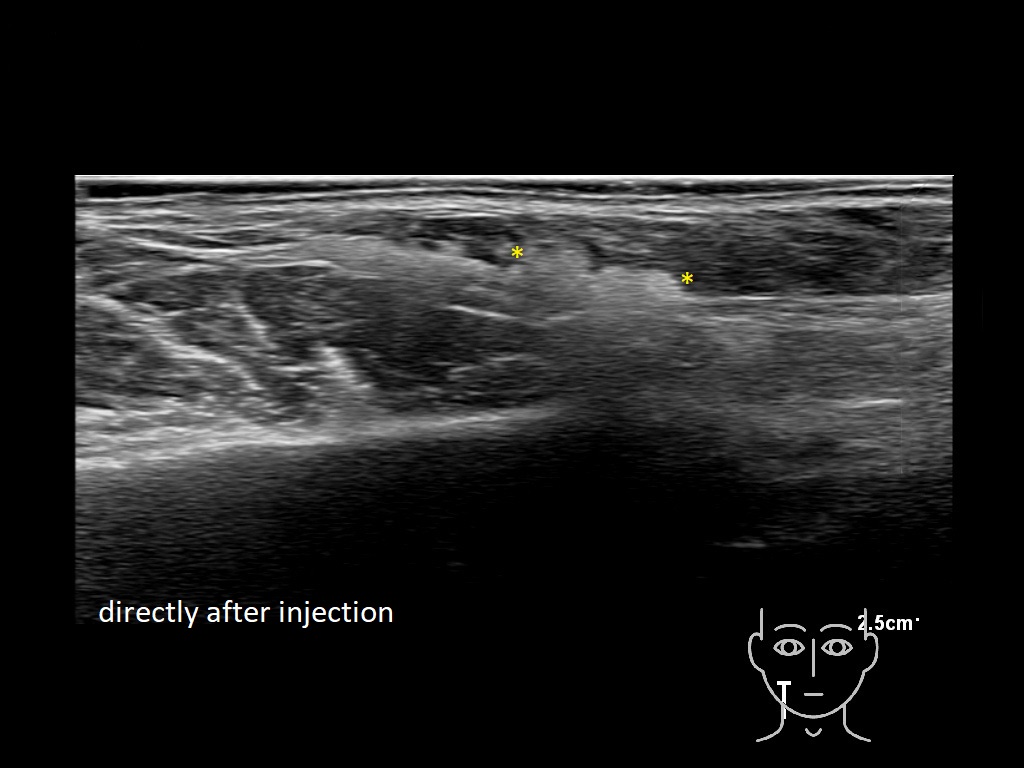

Draw in the image on the right where the fillers are located. To check if your answer is correct, please click on the secondary image.

Fillers

Draw in the second image below where the fillers are located. To check if your answer is correct, swipe the first image to the right.